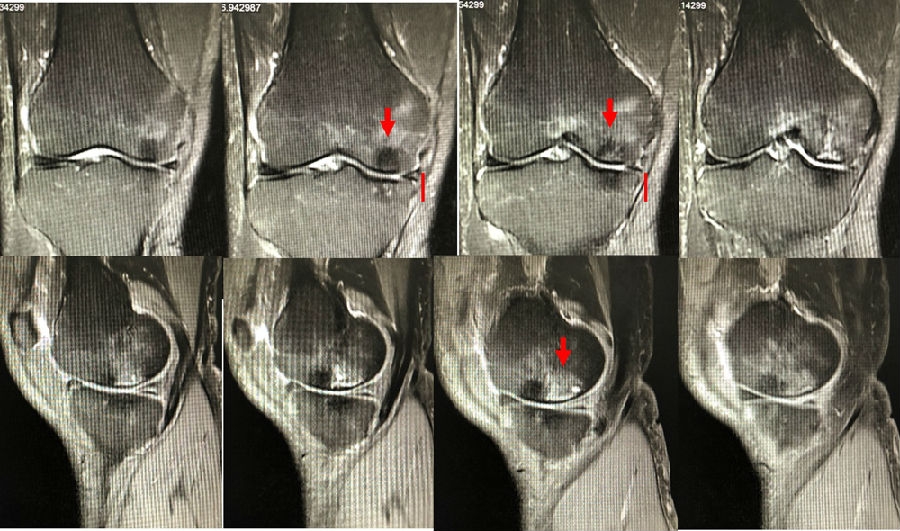

病例1:女,65岁,主诉右膝关节内侧疼痛1周。2018年1月X光未见右膝骨质异常,MR检查见股骨内侧髁骨坏死,半月板相对突出百分比(RPE)28.99%,关节线会聚角1.4°。

予切开行克氏针钻孔减压,口服消炎止痛药物、钙剂及骨化三醇,不负重6周,后改部分负重至3个月。2018年4月复查MR见骨髓水肿基本完全吸收,坏死区局限并修复良好,半月板相对突出百分比(RPE)32.08%,患者临床症状消失。

病例2:女,69岁,主诉左膝关节内侧疼痛1月余。2017年11月X光见右膝股骨髁负重区的软骨下区域出现了椭圆形透亮影,MR检查见股骨内侧髁骨坏死,合并内侧半月板外突和后角层裂,半月板相对突出百分比(RPE)25.32%,矢状位病变区域前后径为23.96mm,关节线会聚角6°。

予克氏针钻减压,消炎止痛药物口服、静滴唑来膦酸钠注射液,避免负重6周,后改部分负重至3个月,患者依从性差。2018年1月复查MR见骨髓水肿少许吸收,坏死区扩大,半月板相对突出百分比(RPE)33.53%,矢状位病变区域前后径为26.89mm,患者仍有膝关节疼痛症状,建议行手术治疗,患者拒绝手术后失访。

病例3:男,70岁,主诉右膝关节疼痛1年余。查体右膝无肿胀畸形,膝活动度0-120°,内侧间隙压痛。

已经累及44%的股骨内侧髁病变,半月板轻度突出,内侧后角水平撕裂

MRI上深度>20mm

治疗选择保守还是手术?

保守治疗4个月后复查

保守治疗后效果欠佳,坏死范围扩大、塌陷

翻修手术选择截骨矫形还是单髁置换?

最终选择截骨矫形

术后1年1个月

术后2年1个月拆钉

内侧半月板突出未见明显进展